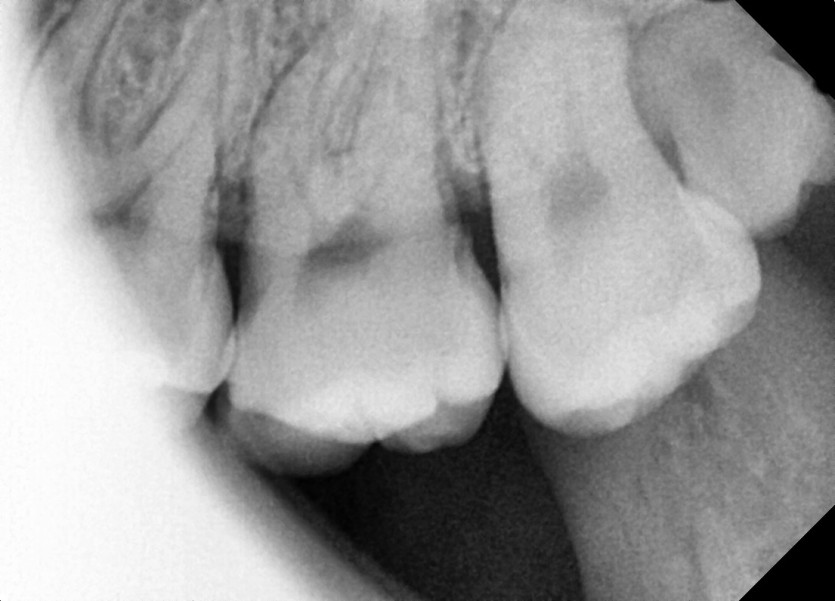

#28,38 사랑니 발치

구강 외과 전문의가 당일 발치했습니다.